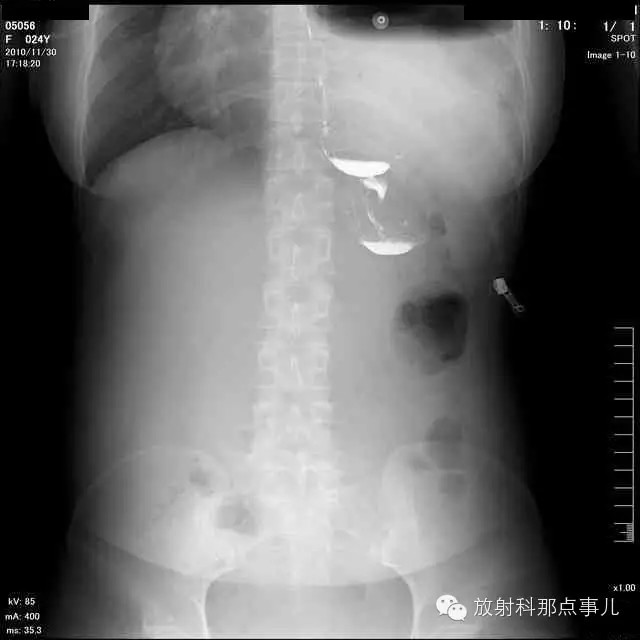

门诊腹部透视发现左侧胸腔巨大气液平面,为排除膈疝口服钡剂,但造影剂未见进入胃内。嘱住院,外科给予胃肠减压、补液等处理常规处理(未引流出明显气、液体)。5个半小时后再次检查,见少量造影剂进入消化道;为进一步了解情况,予泛影葡胺分别经胃管推注及口服,但均未进入胃内。当天进行外科急诊手术。

更正:检查时间在左上方。

大部分胃、脾及横结肠均经过胸肋三角疝入左侧胸腔内,并见疝环形成。